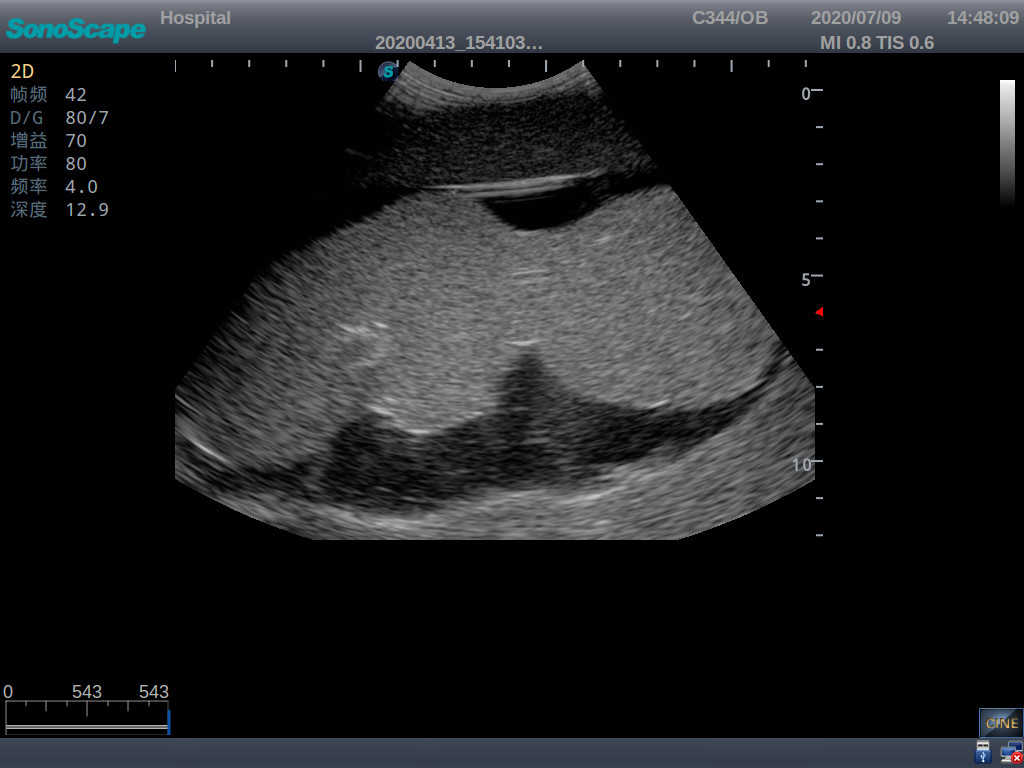

· High-quality ultrasound images for users to recognize 22-week fetus, placenta, placenta, umbilical cord and amniotic fluid